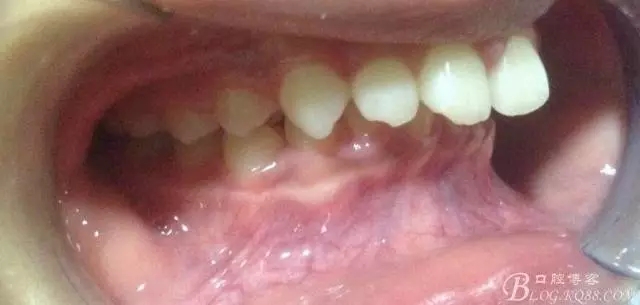

看看口內(nèi)照吧!真象“大暴牙”v假象“大暴牙”

三度深覆合,三度深覆蓋,尖牙,磨牙均二類關(guān)系!